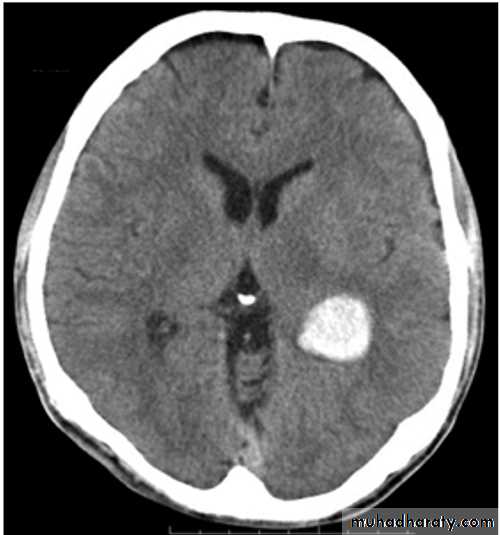

CNS bleeding is the most dangerous form of bleeding & always should be suspected in hemophilic pt. with headache or other neurological symptoms.

Ct scan : bleeding